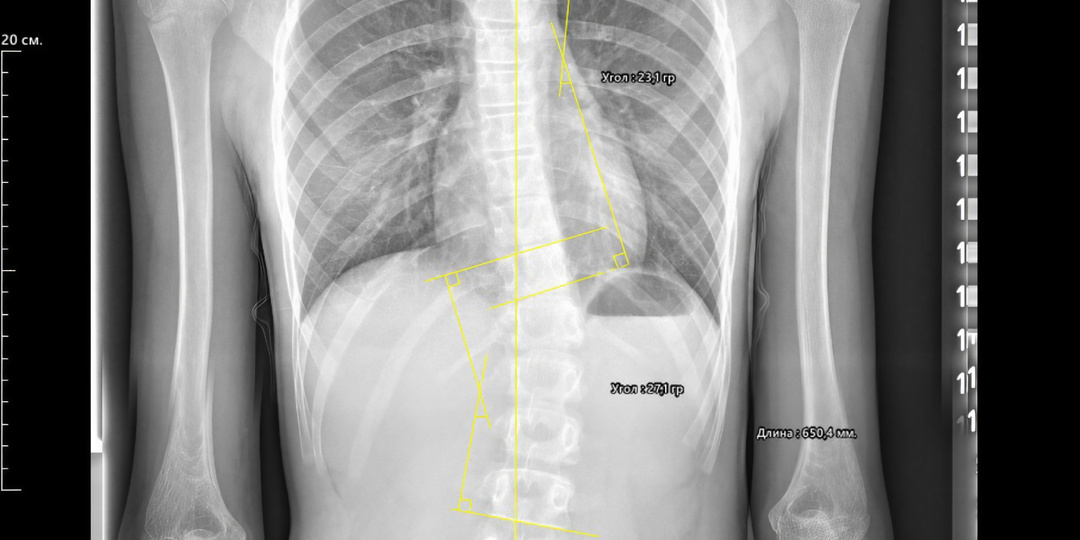

В начале 2024 года к нам обратилась 13-летняя девочка. Ситуация была критической: по результатам обследования в поликлинике произошла резкая прогрессия сколиоза. На момент начала лечения данные были такими: • Тест Риссера: 0 (активный рост!) • Сколиотические дуги: Правосторонняя грудная 23° и Левосторонняя поясничная 27°. ВАЖНО! Угол Кобба 27⁰ классифицируется как III степень сколиоза (пограничная или начальная III степень), что требовало немедленного и очень строгого вмешательства. Рекомендации: Строгое ношение корсета Шено + ежедневная специализированная Шрот-гимнастика. 🔥 Секрет успеха? Дисциплина и вера! 🔥 Эта девочка — настоящий герой! Столкнувшись с диагнозом III степени, она не опустила руки и добросовестно выполняла ВСЕ рекомендации: • Строгое ношение корсета положенное время. • Ежедневные, усердные занятия Шрот-гимнастикой. И знаете что? С каждым контрольным снимком результат становился лучше и лучше! 🏆 И вот он, наш фантастический результат! 🏆 На последне